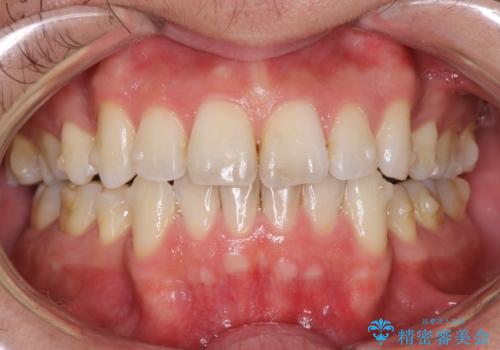

矯正治療の開始前にPMTCで汚れの除去

- これから矯正治療が開始される方です。装置の作成前にクリーニングを希望とのことでした。PMTC30分コースを行いました。

プラーク(細菌の塊)や歯石がたまると歯の表面はザラつきいてきます。そのザラつきは歯周病や虫歯菌の棲家となります。そのまま放置すると、歯肉が腫れてきたり、歯肉から出血したり、口臭が強くでたりします。とくに歯肉の境目は、歯磨きで汚れを除去することが難しく、プラーク(細菌の塊)や歯石が溜まりやすい場所です。

歯並が、がたついている場合はなおさら汚れが溜まりやすいです。矯正治療前や定期的にPMTCをすることで、矯正治療中の歯肉トラブルを防ぐことにつながります。